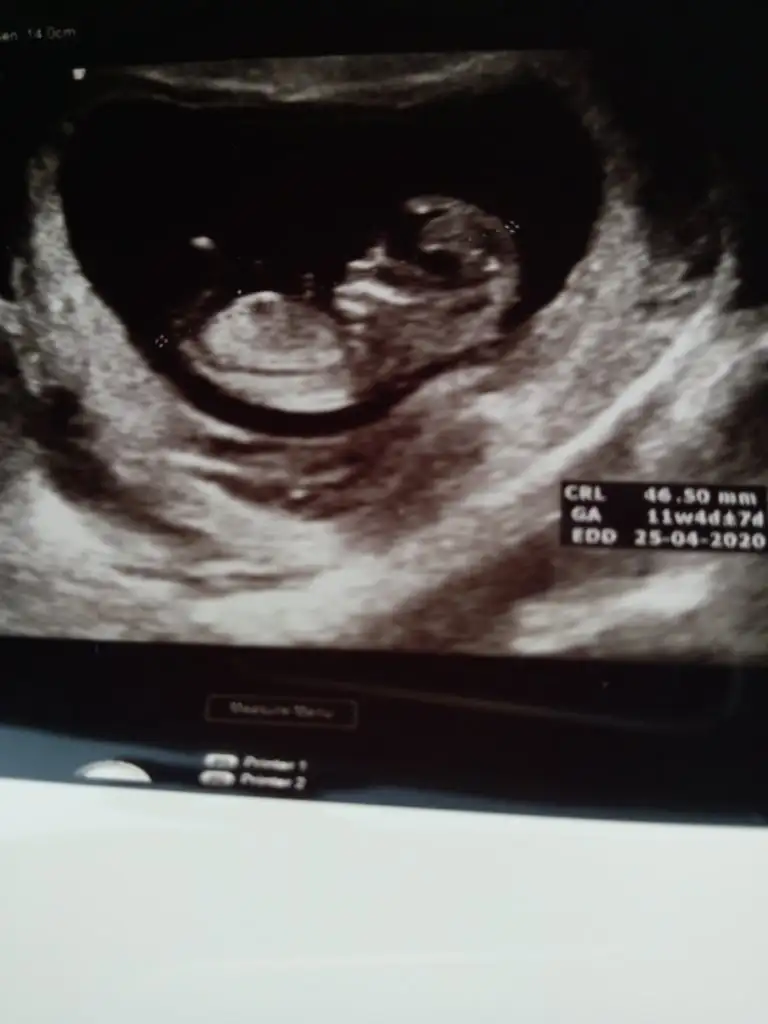

Başka usg varmı net degil usg